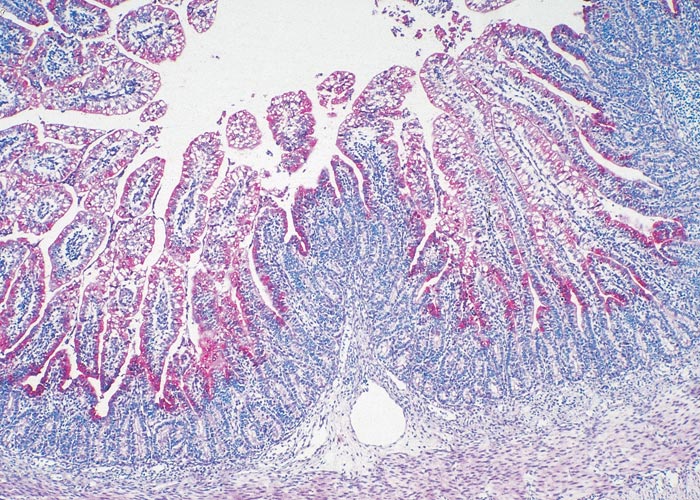

Many C. suis infections are thought to be mild or asymptomatic. Some studies have indicated that C. suis is not a significant pathogen, as it can be isolated from normal and diarrhoeic pigs at the same rate.95, 152 On the other hand, C. suis was the only potential pathogen isolated from four 30-day-old piglets suffering from diarrhoea.94 In another trial, inoculation of gnotobiotic piglets with C. suis resulted in diarrhoea and extensive villous atrophy of the ileum and distal jejunum.114 (Figures 5 and 6). Inoculation of 21-day-old piglets raised conventionally with the same isolates produced only moderate villous atrophy in the absence of clinical diarrhoea.116 The role that colostral antibodies to C. suis may play in moderating intestinal disease in animals of that age is unknown, and it is not clear what synergistic effect chlamydial infection may have with other pathogens. Recent studies with Salmonella typhimurium and Eimeria scaba have shown that the diseases produced by those organisms were more severe when chlamydia was present.72, 106

Figure 5 Chlamydial antigen in a villus of the ileum (four days post-infection) of a gnotobiotic piglet infected with C. suis. The chlamydiae are stained red (ABC-alkaline phosphatase stain)